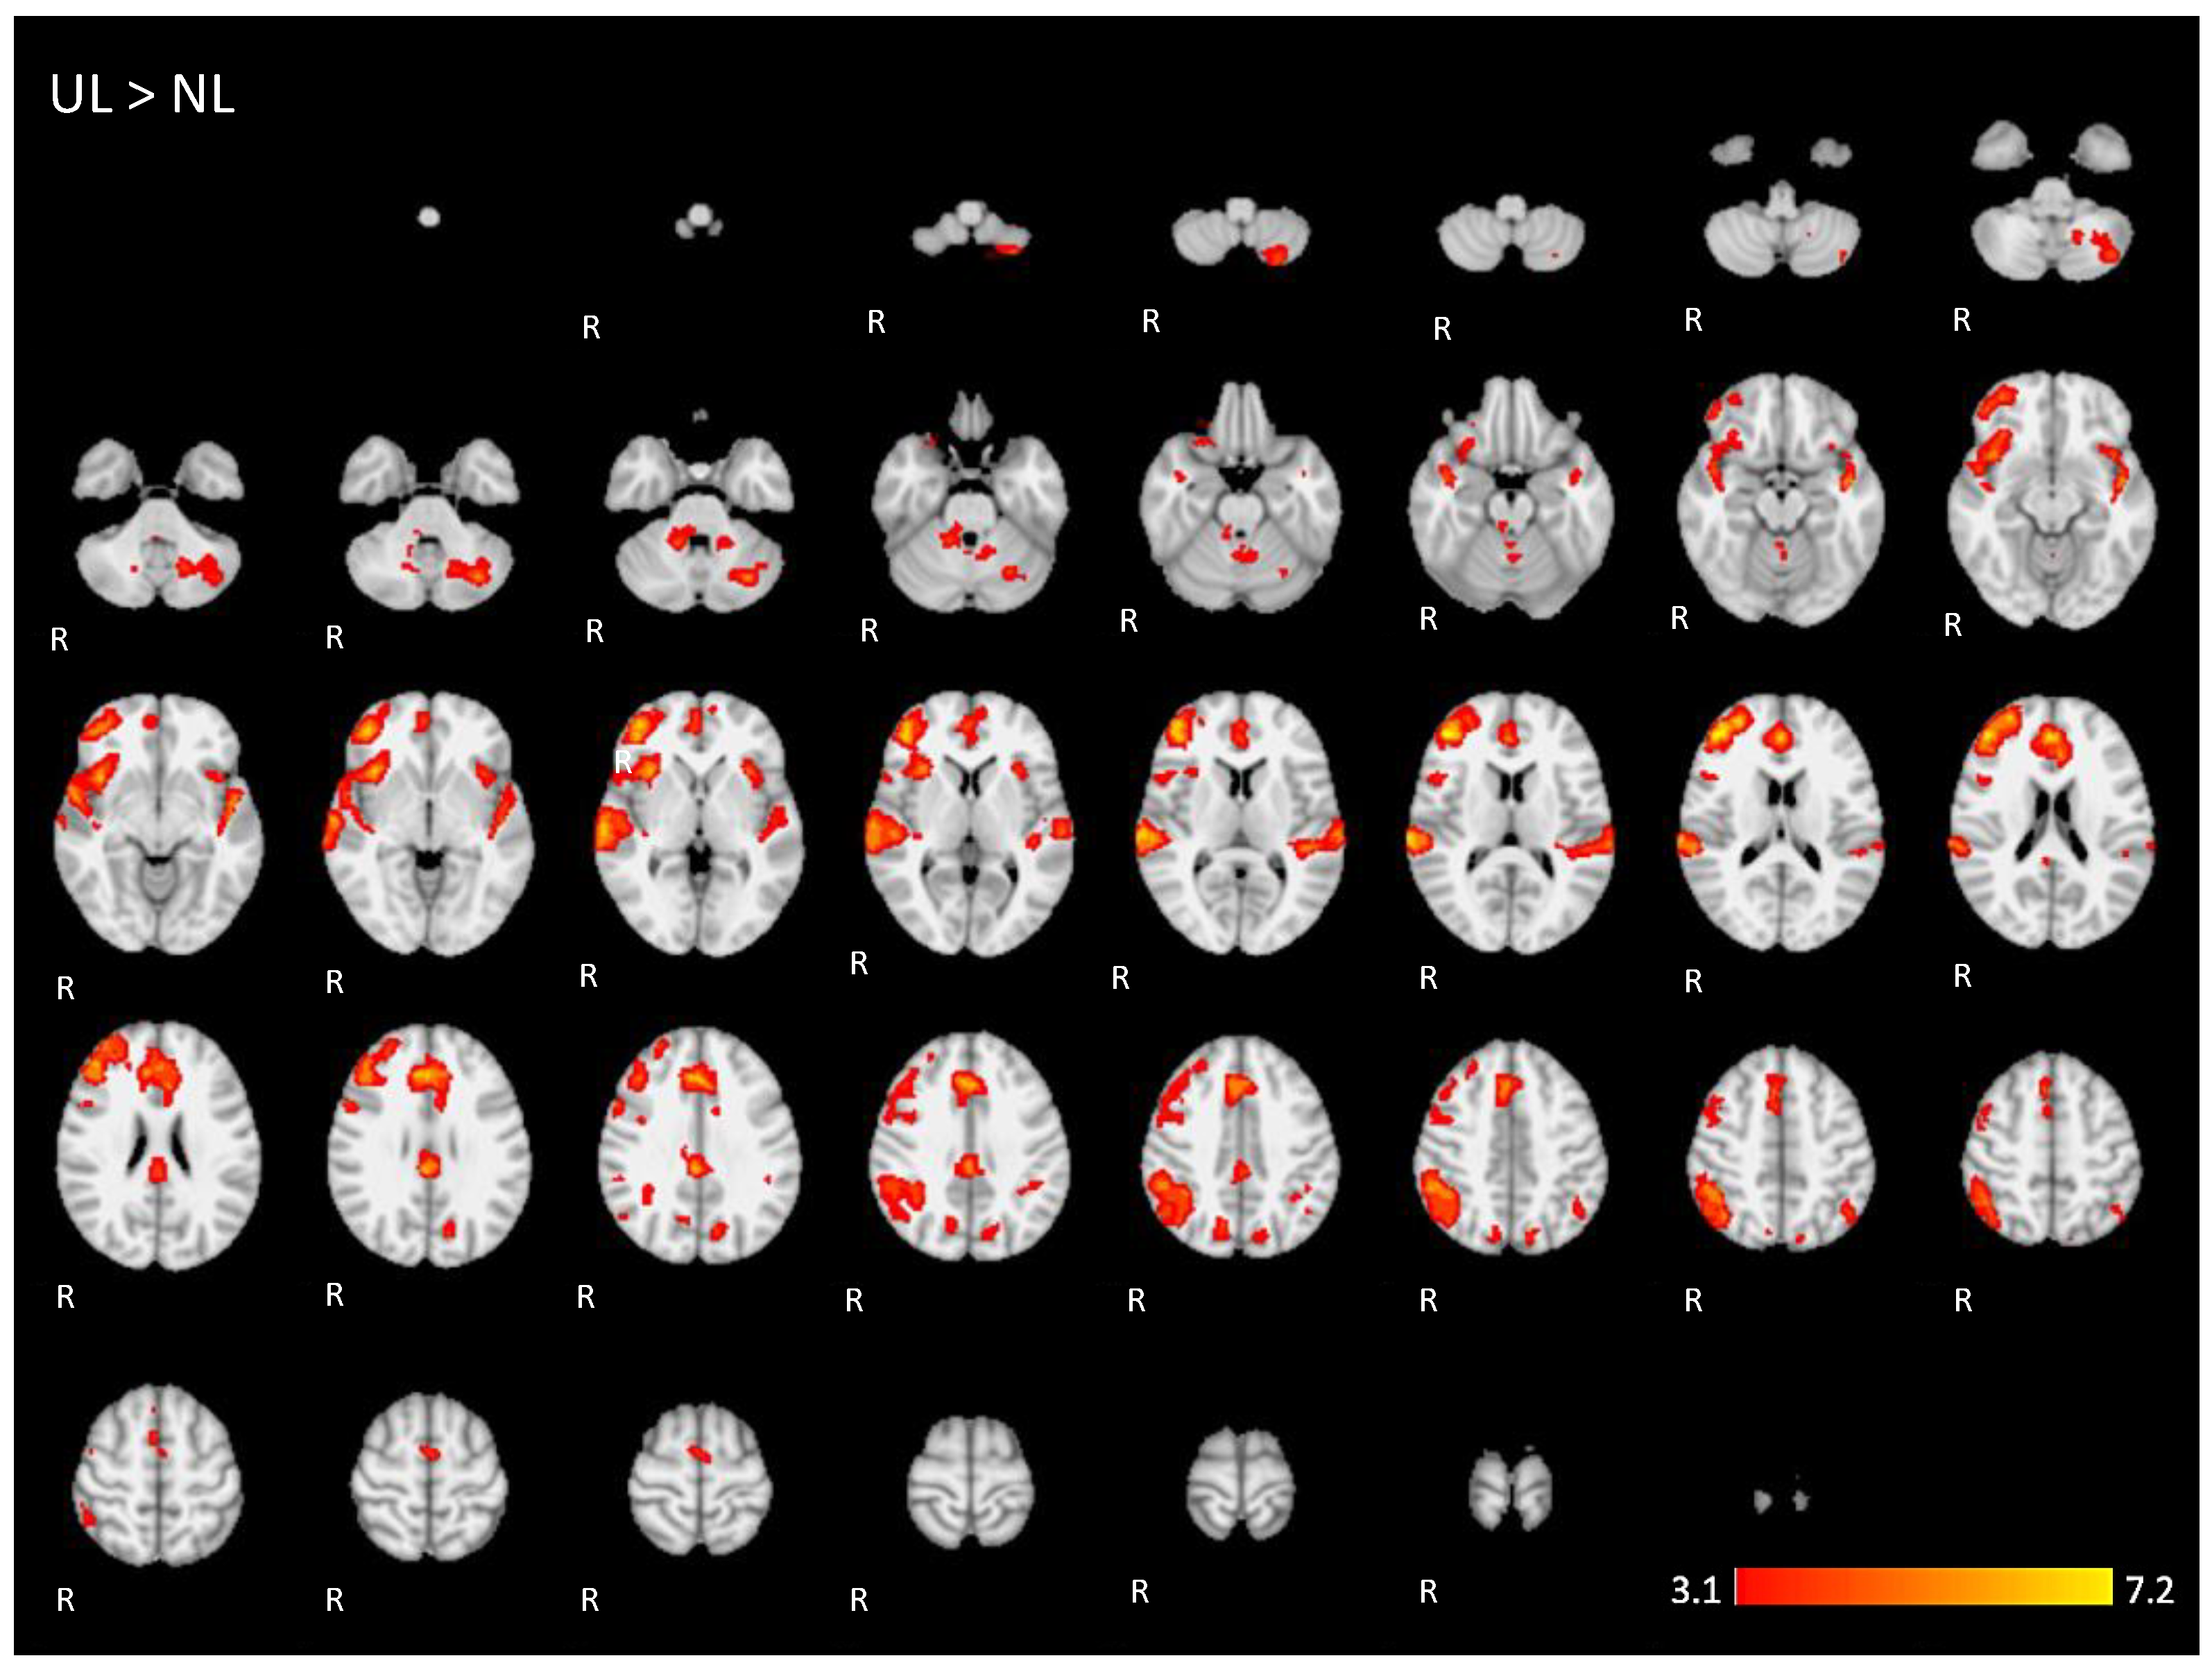

For the contrast (UL > NL), activation was found in additional regions from the dorsal language network and multiple demand networks, such as the angular and supra-marginal gyrus in the bilateral inferior parietal cortex, the bilateral paracingulate and cingulate gyrus, and the bilateral insular cortex (images of fourth line of Figure 5 and Appendix A Figure A4).

The brain activation maps are shown in Figure 5 using the main slices of the 2D fMRI maps for the active conditions NL and UL and for the contrasts NL > UL and UL > NL. The 2D fMRI maps of all brain slices for both active conditions (NL, UL) and for both contrasts (NL > UL and UL > NL) are in Appendix A (Figure A1, Figure A2, Figure A3 and Figure A4, respectively).

Figure A4.

Two-dimensonal fMRI map of auditory attention task (n = 25) for the contrast unknown language (UL) condition higher than native language (NL) condition. (Red–yellow scale indicates the z-score > 3.1; p < 0.05).